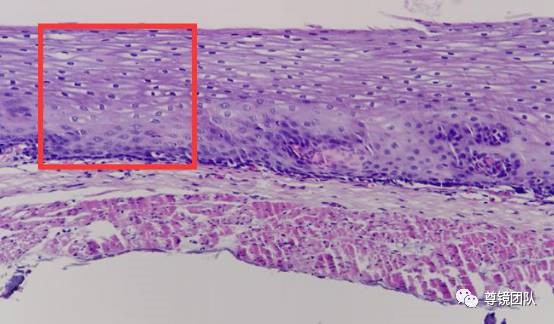

组织胚胎学课件-消化管 1上皮 2固有层 3粘膜肌 6外膜 食管esophagus

所有分类 高等教育 医学 消化系统1ppt 消化系统组织学要点 二,食管

食管下段鳞状上皮被化生的柱状上皮替代;(二) 组织病理学变化:(一)